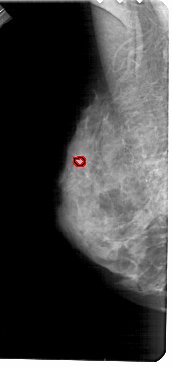

A_1684_1.LEFT_MLO

LEFT_MLO LINES 5491 PIXELS_PER_LINE 2566 BITS_PER_PIXEL 12 RESOLUTION 43.5 OVERLAY

FILE: A_1684_1.LEFT_MLO.OVERLAY

TOTAL_ABNORMALITIES 1

ABNORMALITY 1

LESION_TYPE CALCIFICATION TYPE PLEOMORPHIC DISTRIBUTION CLUSTERED

ASSESSMENT 4

SUBTLETY 2

PATHOLOGY BENIGN

TOTAL_OUTLINES 1